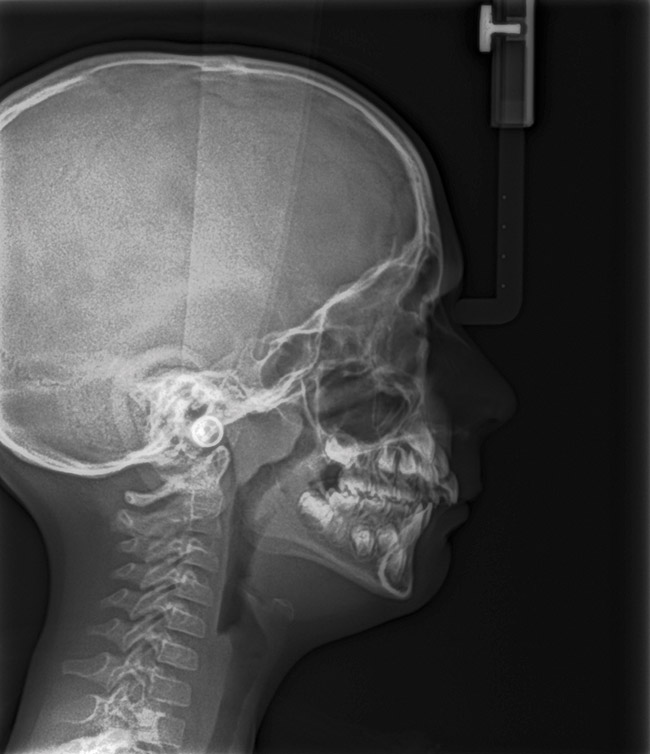

(21.) Six-year-old male presents nocturnal bruxism, habitual snoring, and behavioral issues. PSG reports an AHI of 9.6/hr and respiratory effort–related arousal (RERA) of 14.2/hr (Case provided by Kathy French, DDS).

Figure 21

(22.) Radiograph highlights the obstructed nasal airway preoperatively. Three months after T&A, another PSG demonstrated an AHI of 0.3 and RERA of 0.0/hr.

Figure 22